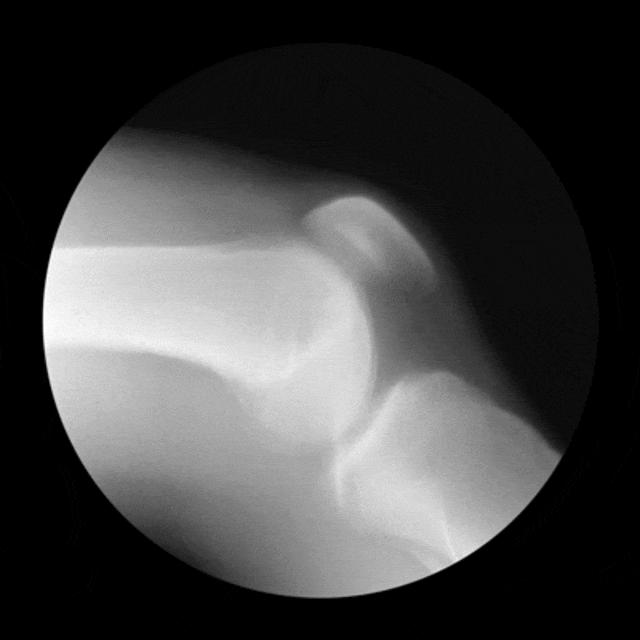

但很少有人知道,膝关节由股骨、髌骨、胫骨、韧带、半月板、滑膜等多个结构组成,疼痛可能是上面任何一个部位受伤造成的。

膝关节软骨损伤分为两大类:慢性磨损退变以及急性外伤导致的软骨剥落。

慢性软骨磨损退变往往是由髌骨关节、股骨髁软骨磨损引起的,是骨关节炎的早期表现。

患者常表现为关节酸痛、局部压痛、上下楼梯痛、膝内侧酸痛等。症状会随着时间的推移而逐渐加重,患者出现久坐后站不起来,变天时膝关节不适,活动后有所缓解,但是活动久了又出现不适。